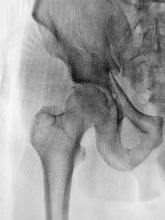

Supplemental Vitamin D Fails to Lower Fracture Risk

NEJM has published study results showing that vitamin D3 supplementation does not significantly lower fracture risk (vs. placebo) when used in generally healthy adults.